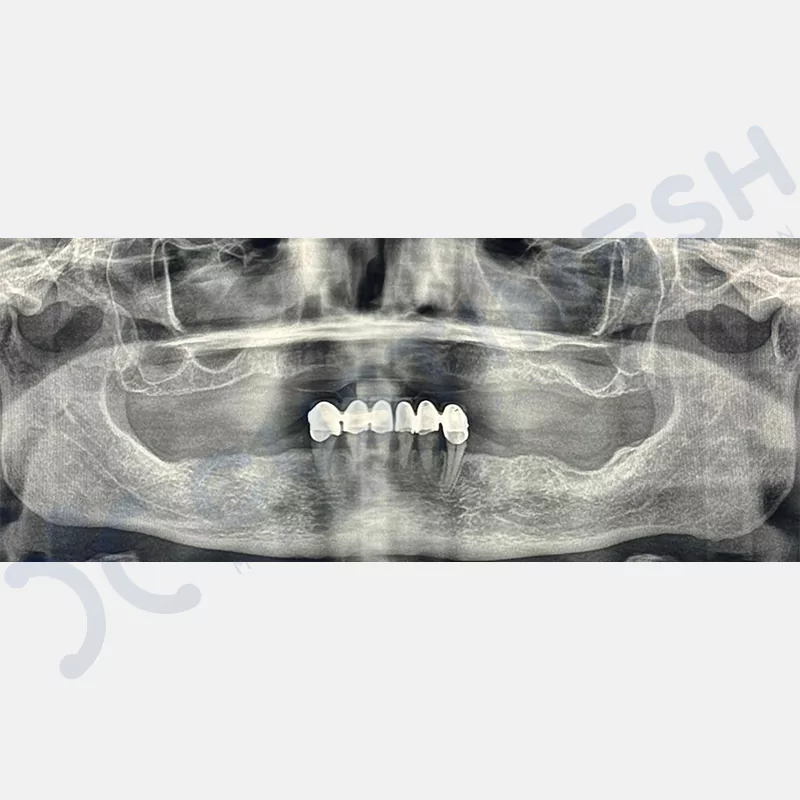

Modern diş hekimliğinde, çene gelişimini tamamlamamış veya ciddi kemik kaybı yaşayan hastalar için kişiye özel titanyum implantlar ile çözüm bulunmaktadır. CAD/CAM teknolojisi ve lazer sinterleme yöntemiyle üretilen bu implantlar, hastanın bireysel anatomik yapısına tam uyum sağlayarak geleneksel implantların uygulanamadığı vakalarda mükemmel bir alternatif oluşturmaktadır. Özellikle ileri derecede kemik kaybı olan hastalar için geliştirilen subperiosteal implantlar, periostun altına yerleştirilerek minimal invaziv bir yaklaşım sunarken, bilgisayarlı tomografi verileri ve sonlu eleman analizleriyle optimize edilmiş tasarımları sayesinde hem estetik hem de fonksiyonel sonuçlar garanti etmektedir. Bu yenilikçi teknoloji, tek seansta implant ve protez uygulamasına imkan vererek hastaların aynı gün doğal gülüşlerine kavuşmalarını sağlarken, kemik greftleme gibi ek işlem ihtiyacını ortadan kaldırarak cerrahi süreci büyük ölçüde kolaylaştırmaktadır. Kişiye özel tasarımı ve üstün biyouyumluluğu sayesinde, daha önce tedavisi mümkün görülmeyen kompleks vakalarda bile başarılı sonuçlar sunan bu implantlar, modern diş hekimliğinde yeni bir çağ açarak hastaların yaşam kalitesini artırmayı hedeflemektedir.

VAKA 3